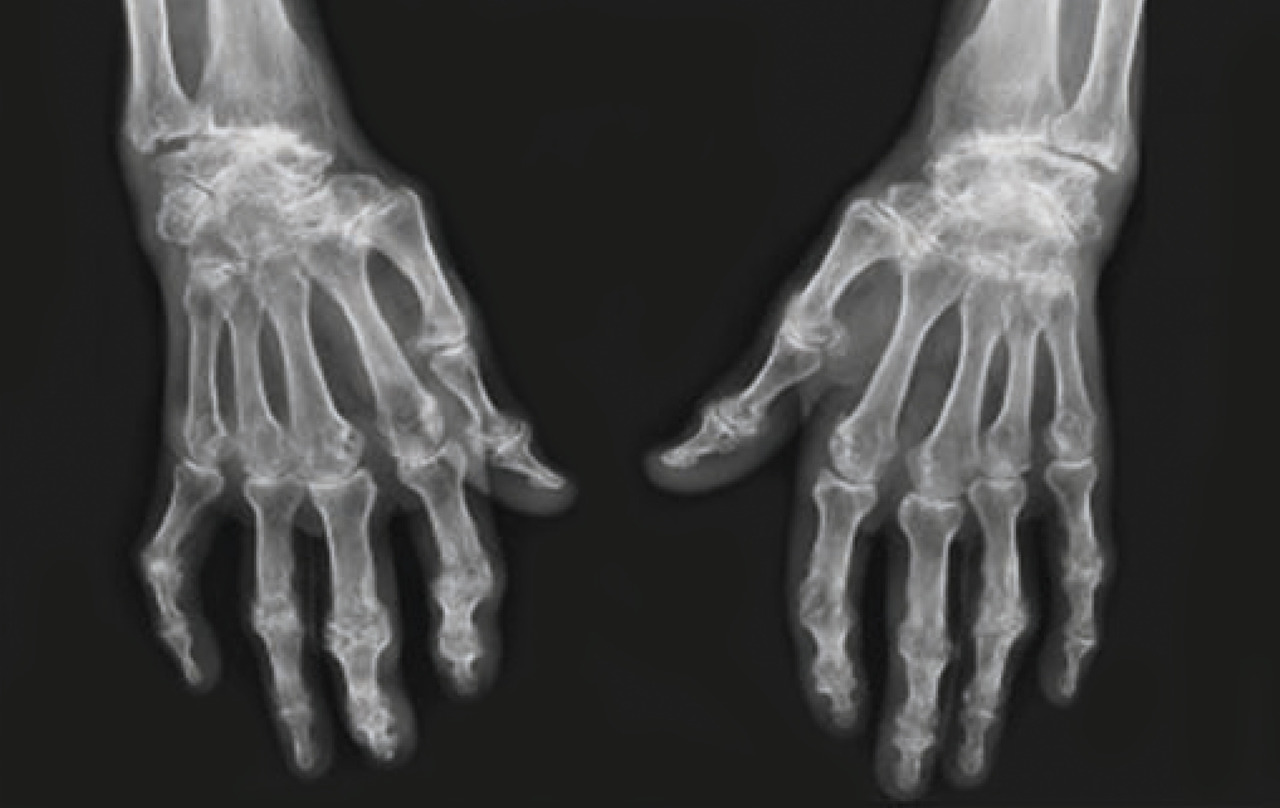

L’évolution naturelle de la polyarthrite rhumatoïde est variable, et 30 % des patients ne présentent qu’une seule poussée. Pour les autres, l’évolution est marquée par des poussées successives pouvant atteindre un plus grand nombre d’articulations. Ces poussées sont plus ou moins sévères et peuvent être entrecoupées de périodes de franche amélioration, voire de rémission clinique. Les mains, les poignets et les avant-pieds sont les sites les plus fréquemment touchés. Les coudes, les épaules, les chevilles, les genoux, les hanches et le rachis cervical peuvent être également atteints. La persistance des synovites favorise la destruction articulaire, qui se traduit radiologiquement par la mise en évidence d’érosions, de géodes et de pincements articulaires diffus (fig. 2). L’aggravation de l’atteinte ostéoarticulaire est à l’origine de déformations et d’une perte de fonction (fig. 3) pouvant nécessiter le recours à la chirurgie (correction, arthrodèse, prothèse) selon le site et le type d’atteinte. Les ténosynovites sont également fréquentes, touchant préférentiellement les poignets et les chevilles. Elles peuvent évoluer vers la rupture tendineuse et être également responsables de déformations.

Le bilan initial systématique comporte des radiographies standard à 100 % des mains et des poignets de face sur la même plaque, des avant-pieds de face et de trois quarts. En fonction de l’atteinte, d’autres clichés centrés peuvent être réalisés. Ces examens peuvent aider au diagnostic et servent, dans tous les cas, de référence pour le suivi du patient. Il peut être mis en évidence une classique déminéralisation en bandes, non spécifique. Exceptionnellement, on observe une ou plusieurs érosions radiographiques précoces très fortement évocatrices du diagnostic de polyarthrite rhumatoïde ou bien un pincement articulaire diffus, et enfin des géodes. Le plus souvent, les modifications radiographiques surviennent secondairement, favorisées par la chronicité des synovites.